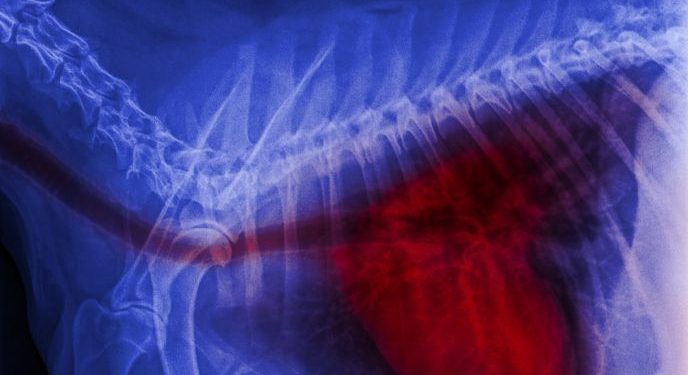

Blastomycosis is most common in the lungs, but it can also affect other parts of the body. In some cases, the infection can spread to the brain. It can also lead to meningitis or epidural abscess. Patients with blastomycosis often have a weak immune system, and they will require close monitoring to prevent a relapse.

The most common sites where this infection can occur are the lungs, skin, and bones. While the fungus can be transmitted by direct contact, it can also be passed on through the blood or by breathing in spores. Symptoms can be very similar to those of other diseases, including TB.